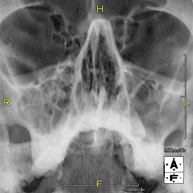

Tècnica que usa els raigs X a través de la qual s'obtenen imatges del crani per al seu estudi. Indicacions: traumatisme, tancament precoç de sutures cranials. - RX Sins Paranasals

Tècnica que usa els raigs X a través de la qual s'obtenen imatges dels sins paranasals per al seu estudi. Indicacions: dificultat respiratòria nasal, tos crònica, cefalea, mucositat - RX ATM (Articulació Temporo-Mandibular)

Estudi que mitjançant una radiografia de la mà permet valorar, en funció del desenvolupament dels ossos, l'edat del pacient i determinar si existeix un retard o un creixement superior pel que correspon a la seva edat. - RX Sins paranasals

Tècnica que usa els raigs X a través de la qual s'obtenen imatges dels sins paranasals per al seu estudi. Indicacions: cefalea, tos crònica. - RX Tòrax